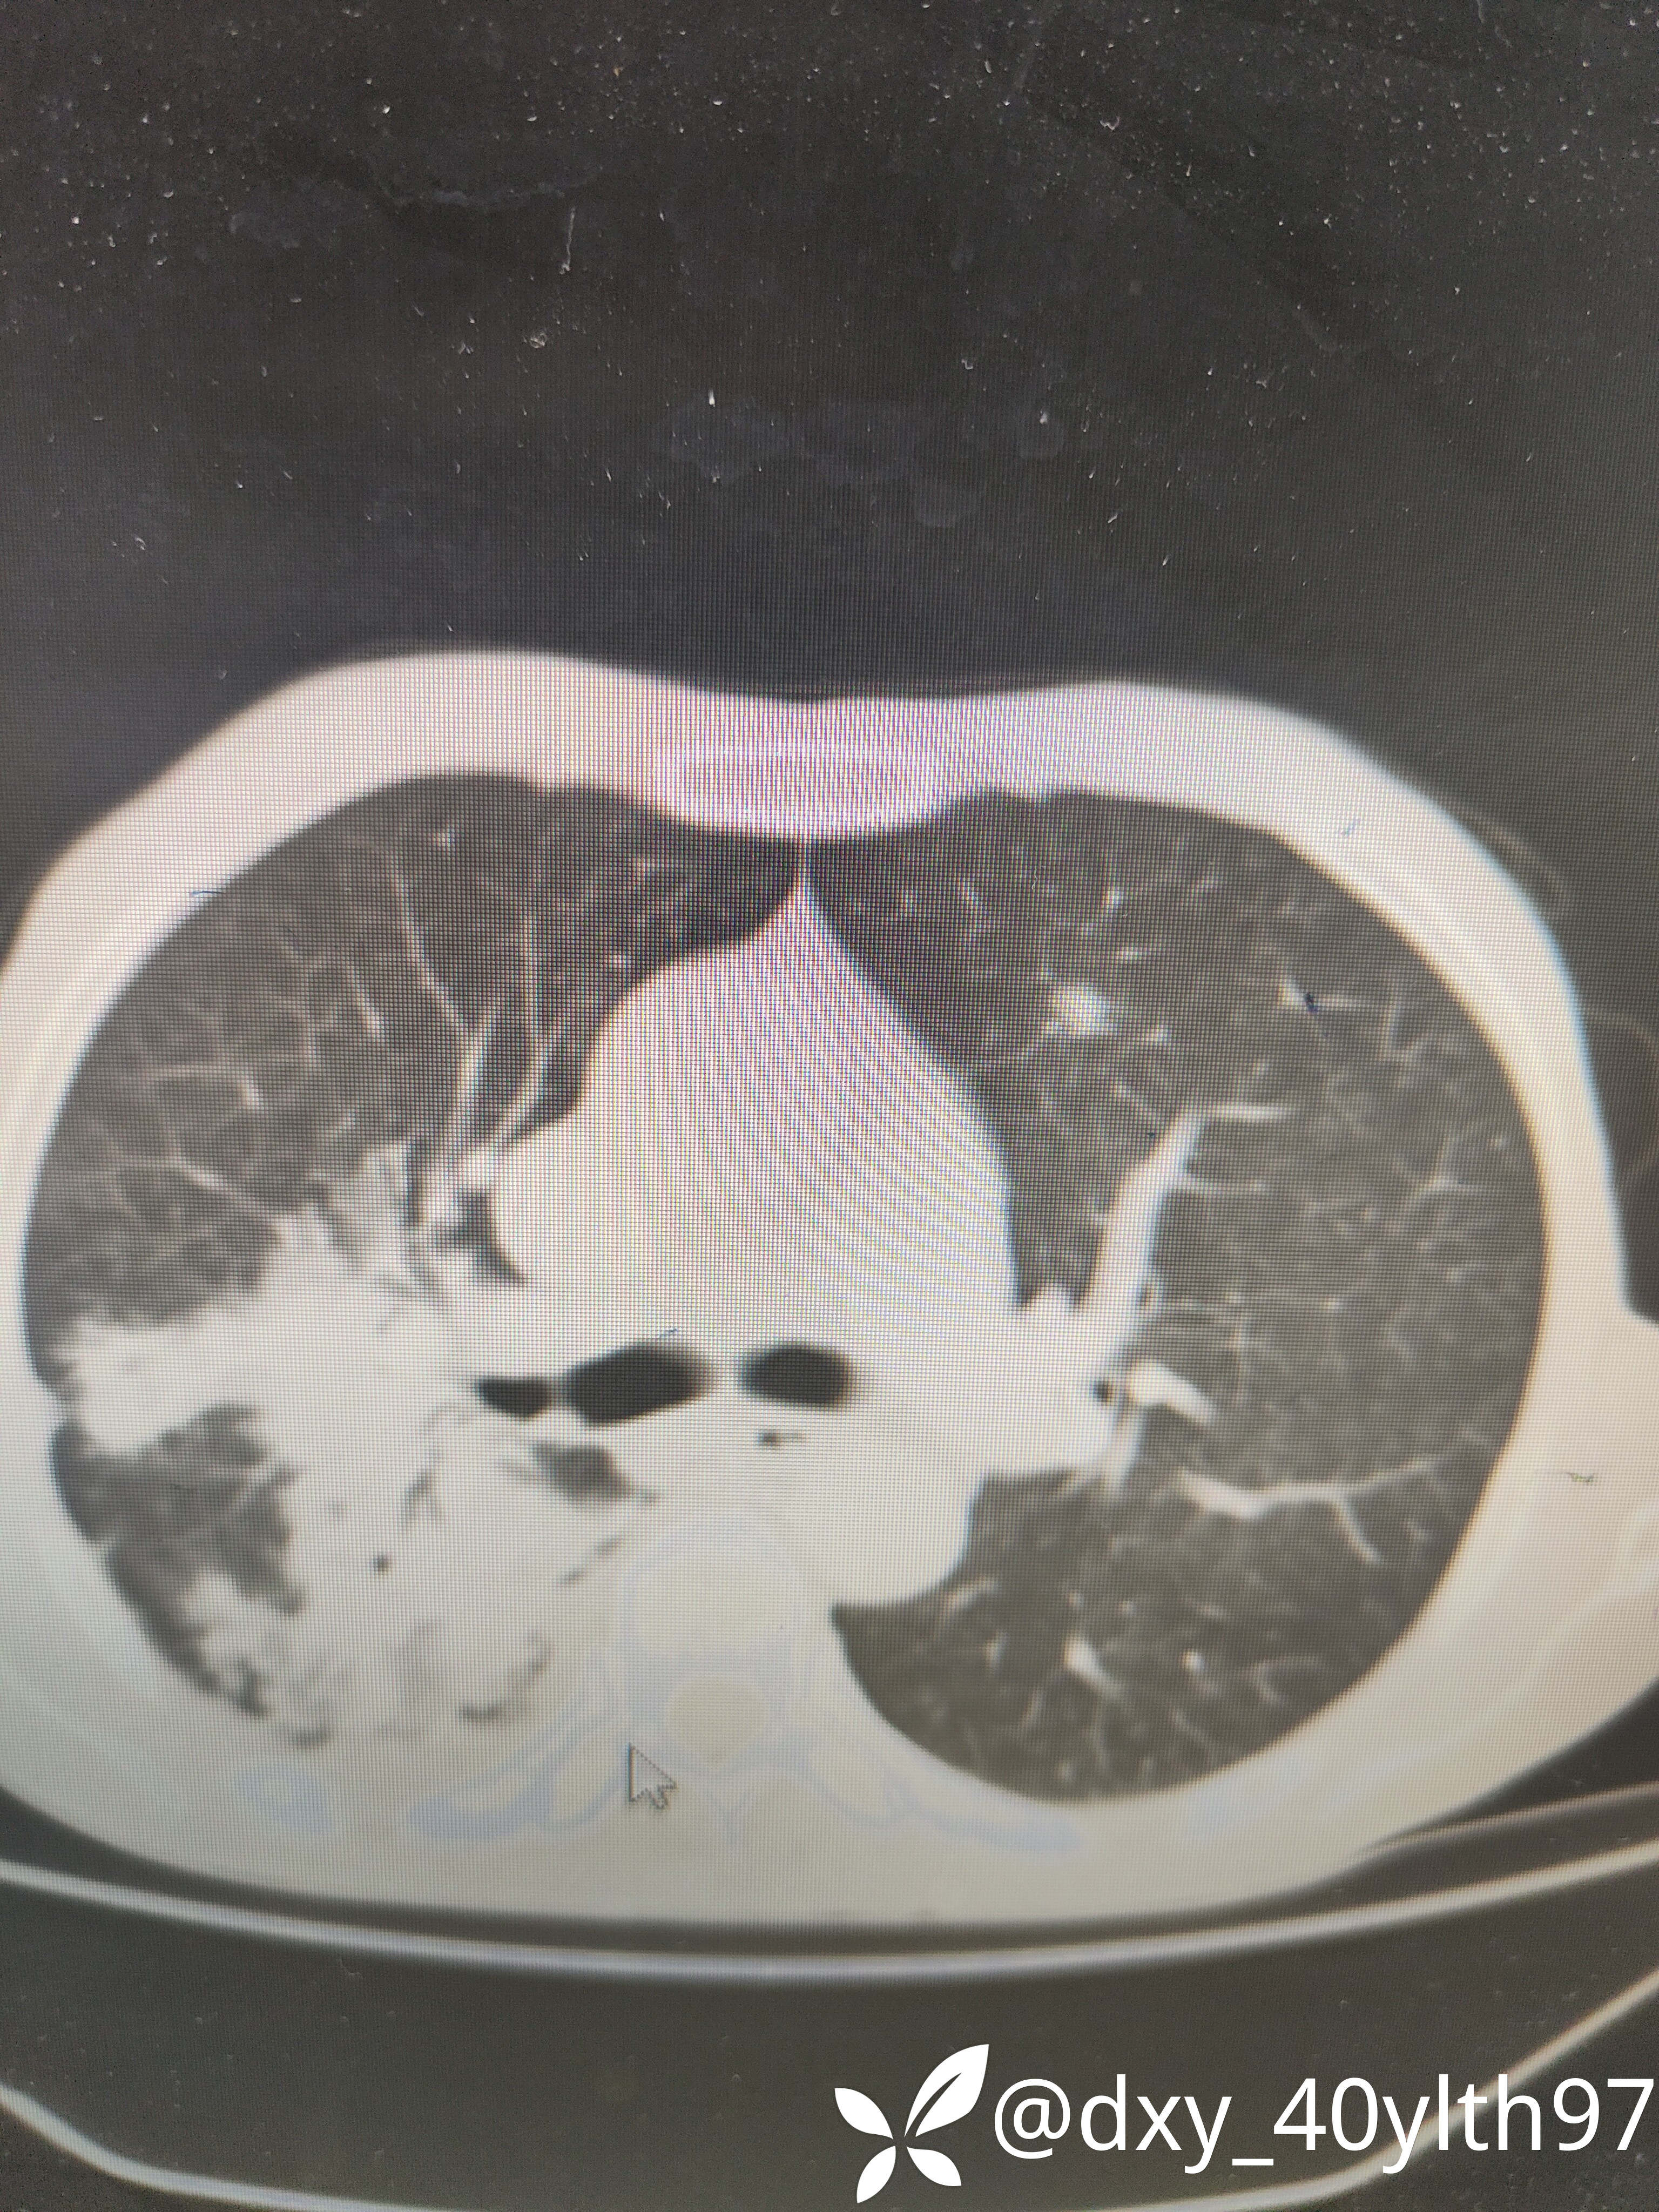

2021年5月首次肺部CT平扫,影像报告提示1.两肺慢性支气管炎、肺气肿、多发肺大疱;2.右肺中下叶多发感染性病变、结节、右肺门增大,建议治疗后复查或进一步检查排查右肺门区肿瘤性病变;3.左肺上段舌叶散在炎性病变

2023年8月肺部CT平扫影像结果提示:1.右肺上叶密度增高影较前显著增大,建议进一步检查;2.两肺多发斑片结节灶较前增多,部分增大。

肺部增强CT影像学提示:右肺内大片不规则影轻度强化,肿瘤可能。

肺穿刺活检病检提示:(右肺活检组织)慢性肉芽肿性伴坏死